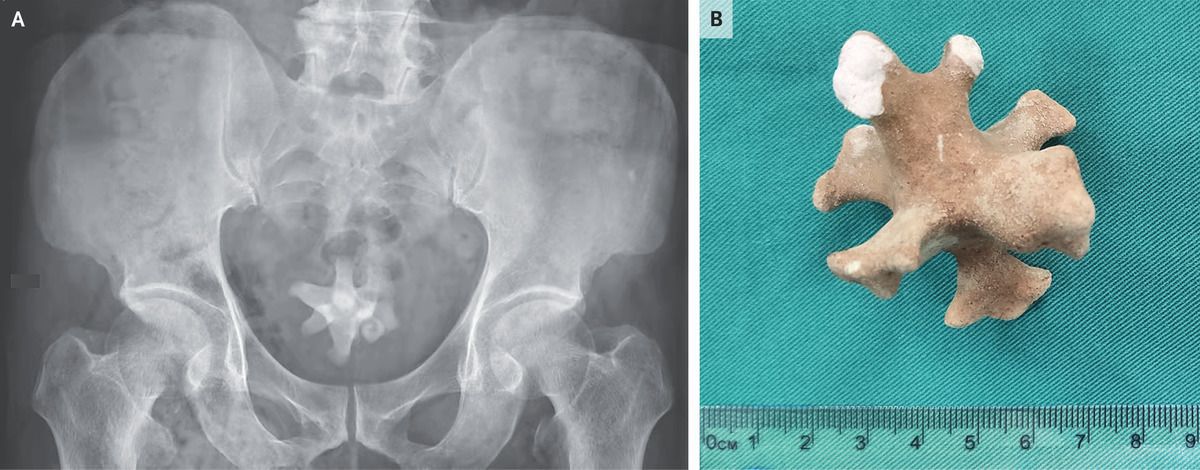

A 70-year-old man was referred to the urology clinic with a 3-month history of worsening symptoms in the lower urinary tract and new-onset hematuria. He had a history of recurrent urinary tract infections and benign prostatic hyperplasia, for which he had previously declined medications. However, 3 months earlier, he had started tamsulosin and finasteride to treat progressive dysuria, nocturia, frequency, and urgency. On physical examination, there was tenderness to palpation over the suprapubic region and an enlarged prostate. Urinalysis showed pyuria, hematuria, and bacteriuria. A urine culture grew extended-spectrum beta-lactamase–producing Escherichia coli, which was treated with ertapenem. Ultrasonography of the kidneys and bladder showed a small diverticulum in the posterior bladder wall and a large echogenic focus, indicating a possible bladder stone. A subsequent abdominal radiograph showed a large, irregularly shaped, radiopaque stone in the pelvis (Panel A). Transurethral enucleation of the prostate was performed, and a jackstone calculus measuring 5 cm in the largest dimension (Panel B) was removed from the bladder. Jackstone calculi — named after a toy jack — typically form in the bladder because of urine stasis and are composed of calcium oxalate dihydrate. At the 1-month follow-up, the patient’s symptoms had abated. Jiyu Zhao, M.D. Xianen Gu, M.Med. Chuiyangliu Hospital Beijing, Beijing, China source: nejm.org